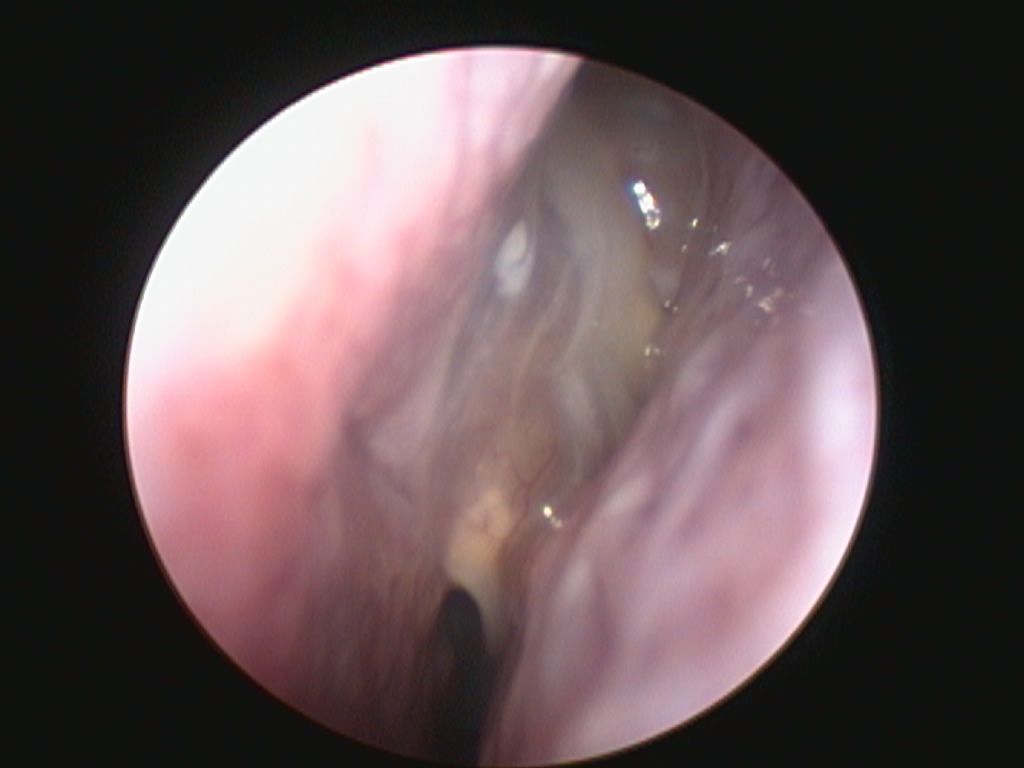

The Research Coalition of the Snot Force Alliance recognized the need for a better way to grade sinonasal polyps after sinus surgery. The standard nasal polyps scales did not adequately measure what otolaryngologists and rhinologists see clinically on endoscopy. The Postoperative Polyps Scale (POPS) was developed to assist otolaryngologists clinically and during clinical trials assessing grade of sinonasal polyposis after surgery.